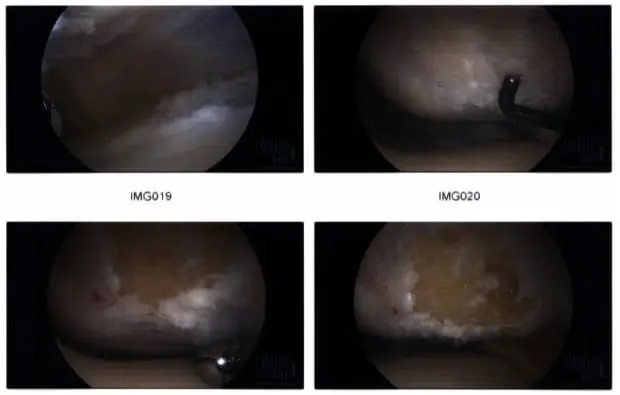

Intraoperative arthroscopic images.